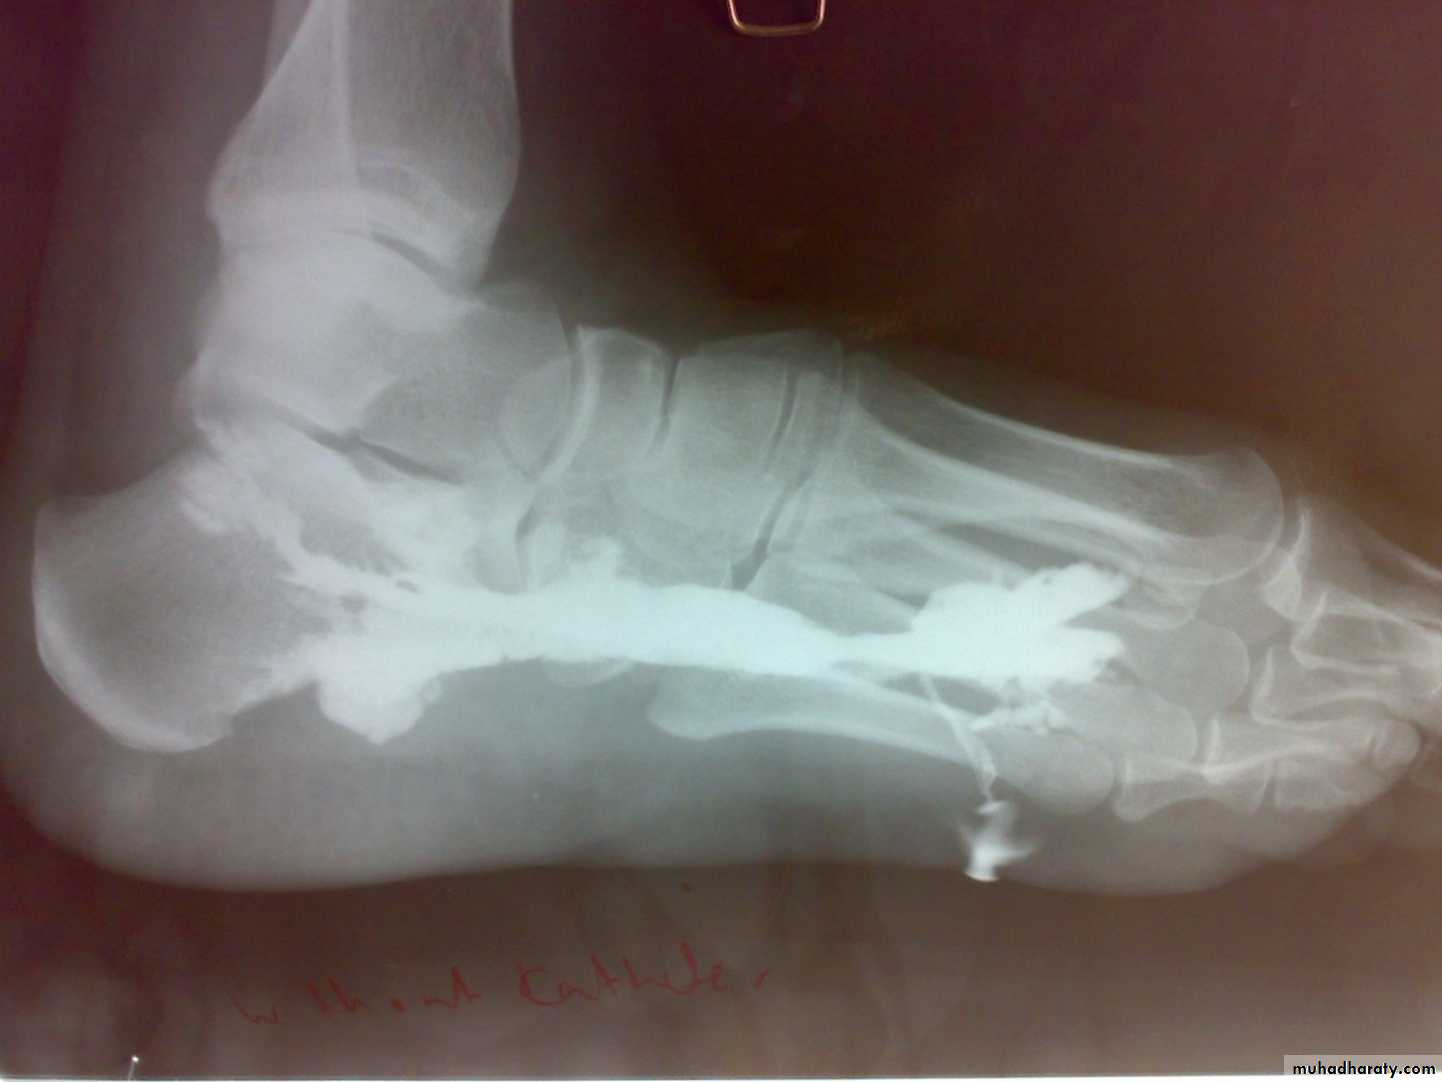

Radiological features

early changes:

Soft tissue swelling, Periarticular osteoporosis

Loclized osteoprosis (Bone ends ‘washed – out’ or localized decalcification ).

Narrowing and irregularity of the articular ends.

Late changes:

Erosions of the subarticular cartilage.

cystic changes appeared.

TB dactylitis – in children hand and feet digits , it should be differentiated from sickle cell anemia,